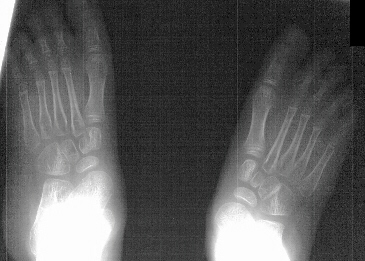

Arthrodesis

of subtalar joint with vitallium staples is another option for

treating this deformity.

A

major problem in any correction of the subtalar joint is midfoot

deformity in the ambulating child with ongoing spasticity. .